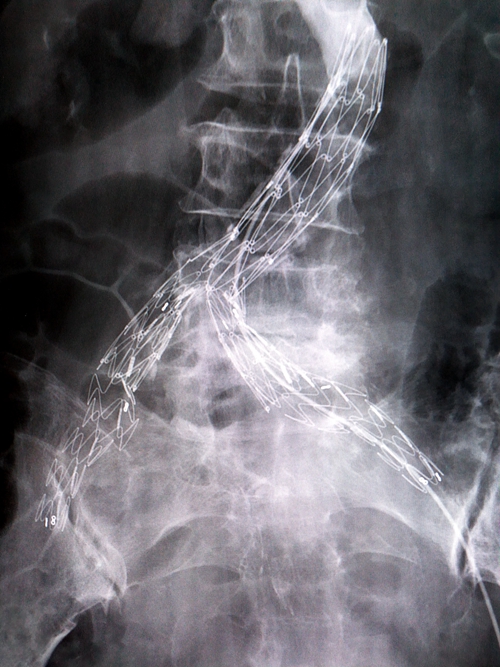

术前髂内动脉造影

支架成功植入

手术在介入手术室进行,由胡康新教授指导,汤金城医生主刀,在DSA引导下,局麻切开右侧股动脉,在超硬导丝引导下置入一体式腹主动脉覆膜支架于腹主动脉末端及双侧髂总动脉内,并在腹主动脉一体式支架远端左右各植入一个覆膜支架,覆盖髂内动脉瘤开口,支架植入后再造影,髂内动脉瘤腔内只少量显影,随着时间的推移双侧髂内动脉瘤开口最终会完全覆盖。手术采取局部麻醉,全程患者并未有痛苦感。经过两个小时的手术,介入医生成功拆除了这两颗“定时炸弹”。